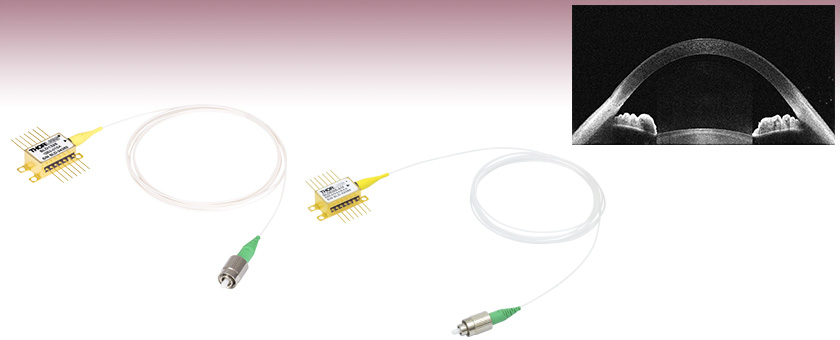

An Image of the Anterior of the Eye Taken with the SLD830S-A10 in a Modified Ganymede System

SLD830S-A10

830 nm SLD, Gain Ripple: ≤0.15 dB

それぞれの画像の組織内深度は6.2 mmで、36 kHzのA-スキャンレートで撮影されています。